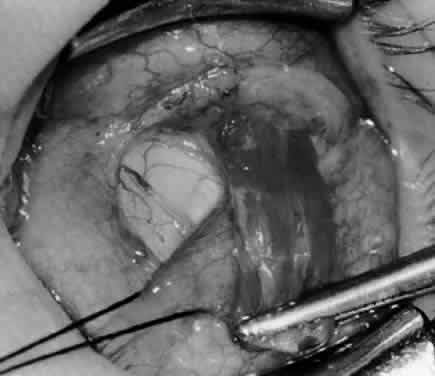

Fig. 3. The eye is retracted superonasally with the 4-0 silk traction suture. The suture is attached to the drapes with a hemostat. A Stevens hook is placed along the inferior border of the lateral rectus muscle and drawn temporally. A von Graefe hook is placed within the incision and drawn inferotemporally to expose the inferior oblique muscle.

Fig. 4. A stiff iris repositor can be placed against the sclera to depress the sclera and enhance the view of the inferior oblique muscle. The inferior temporal vortex vein adjacent to the Stevens hook is retracting tissue along the inferior border of the lateral rectus muscle. The second Stevens hook is pointing to the inferior oblique muscle.

Fig. 5. The Stevens hook is placed adjacent to the posterior edge of the inferior oblique muscle and rotated as the inferior oblique muscle is drawn into the operative field. A forceps is used to retract the redundant Tenon's capsule, encapsulated fat, and intermuscular septum as the muscle is drawn further into the operative field with the Stevens muscle hook.